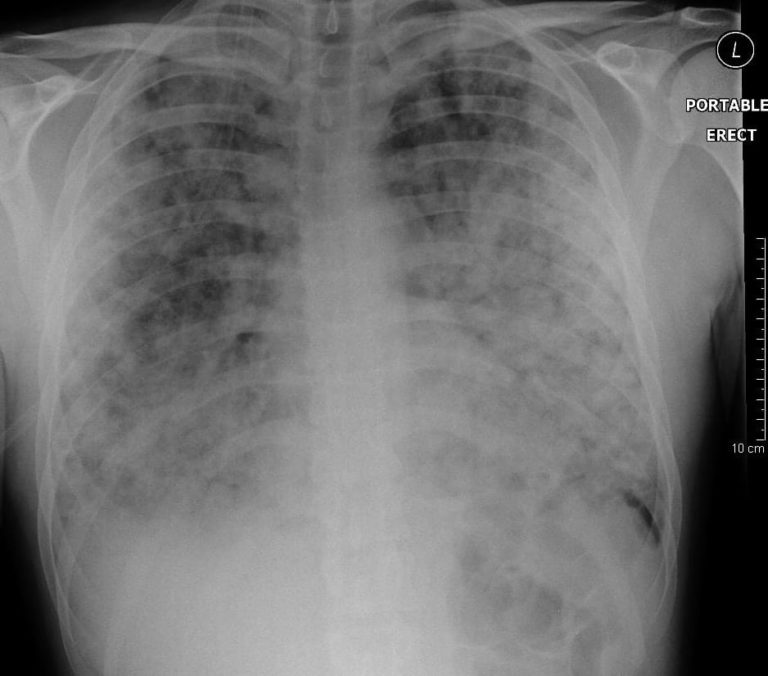

If seen, pulmonary interstitial emphysema .Sinus tachycardia – the most common abnormality (seen in 44% of patients with PE); Complete or incomplete RBBB (18%); Right ventricular strain pattern – T wave inversions in the right precordial leads (V1-4) ± the inferior leads (II, III, aVF).alarmingly high pressures lıtfl pulmonary puzzler. The chest X-ray shows dense consolidation of the right middle lobe.

aka Pulmonary Puzzler 005. Three days previously he was exposed to smoke from a bushfire and has been having difficult breathing since. Her admission chest X-rays are shown below: Questions. In patients with ARDS and/or atelectasis, PEEP may recruit . Agnelli G, Becattini C.

Mechanical Ventilator Alarms | .The use of thrombolytics for the treatment of submassive PE is controversial — the limited documented benefit (e.Pulmonary interstitial emphysema may be seen in roughly half of patients with spontaneous pneumomediastinum.Treatment in this group has been shown to decrease pulmonary artery pressure and improve RV systolic function and pulmonary perfusion; This benefit must be weighed against the risk of haemorrhage with thrombolytic therapy. Alarmingly high pressures . Home LITFL Clinical Cases.Pulmonary Puzzle 014: Alarmingly high pressures: what to do when a high pressure alarm goes off? Which pressures are important? CLINICAL CASES. Three days previously he was exposed .Q&A style clinical cases to assist ‘Just-in-Time Learning’ and ‘Life-Long Learning’ – Pulmonary Puzzler.Chris is an Intensivist and ECMO specialist at the Alfred ICU in Melbourne. Can you figure out why? What are your going to do about it? Paul Young; October 17, 2018; Alarmingly high . High-pressure injection injury in a furniture repairman -an outwardly minor in jury with the potential for . He has been having sudden exacerbations where his chest and throat feels tight and he . Airway pressure is a poor surrogate of lung stress because it ignores the effect of chest recoil aka Pulmonary Puzzler 005. What are you going to do?